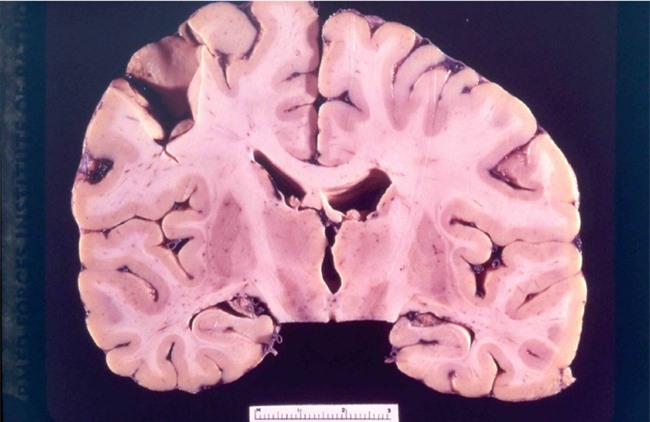

Hình chụp Xquang của bộ não nạn nhân mắc loại bệnh đáng sợ này.

Tuy nhiên, y học ngày ấy lại không đủ khả năng để nhìn ra "thủ phạm" gây bệnh. Sau này khi các loại kính hiển vi hiện đại phát triển, các nhà khoa học đã tìm ra nguyên nhân chính là do prion – một cấu trúc vi sinh vật nhỏ hơn virus tới 100 lần. Đáng sợ hơn, chúng có khả năng chống lại tác động của môi trường và nhân bản rất nhanh, khiến người bệnh cứ vậy mà chết dần chết mòn trong tiếng cười.